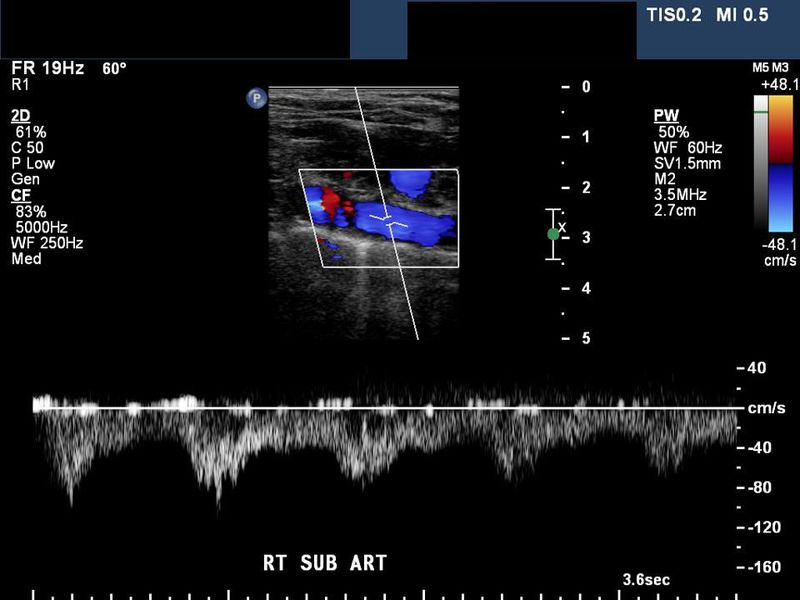

Multiple neck artery disease (stenosis and occlusion) with subclavian steal

Right subclavian artery- reversed flow

Back to top

This patient has multiple level occlusions- the left CCA is occluded as is the ( on the right) innominate or brachiocephalic artery. There is a left subclavian artery stenosis. The left vertebral artery supplies the left ICA via the left ECA (retrograde flow in left ECA). The right vertebral artery (reversed flow) supplies the right subclavian artery as well as the right CCA.  This case and ultrasound/ Color Doppler images are courtesy of Stacey Perrodin, USA.